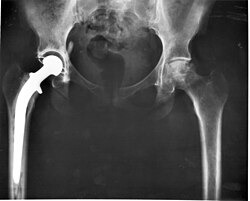

고관절 교체 수술 의 X선 사진

현대의 전체 고관절 교체술은 1960년대 영국의 Wrightington 병원 에서 마찰학 전문가 인 John Charnley 경에 의해 개척되었습니다 . [ 10 ] 그는 관절 표면을 뼈에 고정된 임플란트로 교체할 수 있다는 것을 발견했습니다.그의 디자인은 스테인리스 스틸 , 일체형 대퇴골 줄기와 머리, 폴리에틸렌 아세타불러 구성 요소로 구성되었으며 둘 다 PMMA (아크릴) 뼈 시멘트를 사용하여 뼈에 고정되었습니다 .20년 이상 Charnley 저마찰 관절성형술과 그 파생 디자인은 전 세계에서 가장 많이 사용된 시스템이었습니다.이것은 모든 현대 고관절 임플란트의 기초를 형성했습니다.

엑시터 고관절 치환술 시스템(스템 구조가 약간 다름)이 동시에 개발되었습니다. 찰리 이후, 인공관절 치환술 의 설계와 기술은 끊임없이 발전해 왔으며, RI 해리스의 아들인 WH 해리스를 비롯한 많은 전문가들이 이에 기여 했습니다 . WH 해리스는 하버드 대학에서 뼈가 임플란트에 직접 결합되는 무시멘트 인공관절 치환술 기법을 개척했습니다.